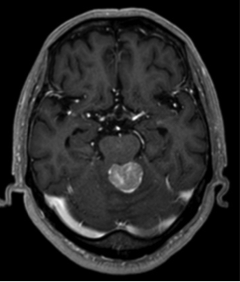

1.髄膜腫

原発性脳腫瘍で最も多い腫瘍ですが、脳そのものから発生するのではなく、脳を包んでいる髄膜から発生します。一般的には良性腫瘍ですが、まれに悪性のこともあります。大きくなると頭痛や麻痺などの症状が出ますが、症状がなくてCT・MRIなどの検査で偶然見つかる場合もあります。小さい場合は経過観察することが多いですが、大きい場合は手術が必要になります。また手術で取り切れない場合や、部位的に摘出困難な場合はサイバーナイフ・トモセラピーによる定位放射線治療を行う場合もあります。

手術前